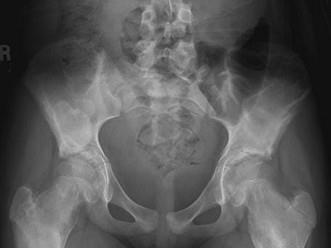

问题 女,12岁,脊柱侧弯畸形,双下肢长短不一,请结合影像图像,最可能的诊断是 ( )

选项 A、非骨化性纤维瘤 B、Paget病 C、骨巨细胞瘤 D、内生软骨瘤 E、骨纤维异常增殖症

答案 E